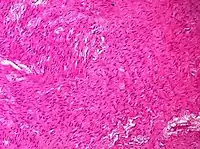

Sex cord-stromal tumor | Ovarian fibroma | 1.5% | 0% | Spindle-shaped fibroblastic cells and abundant collagen.[8] | ![]() |